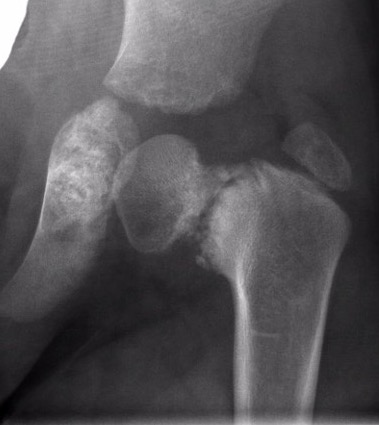

Xray

| Varus femoral neck | Inverted Y | Hilgenreiner's epiphyseal angle |

Neck-shaft angle < 125°

Normal is 150° in infant |

Inferior sclerotic metaphyseal triangle

Pathognomonic of developmental |

Angle between Hilgenreiner's & physeal line

Normal < 25°

|